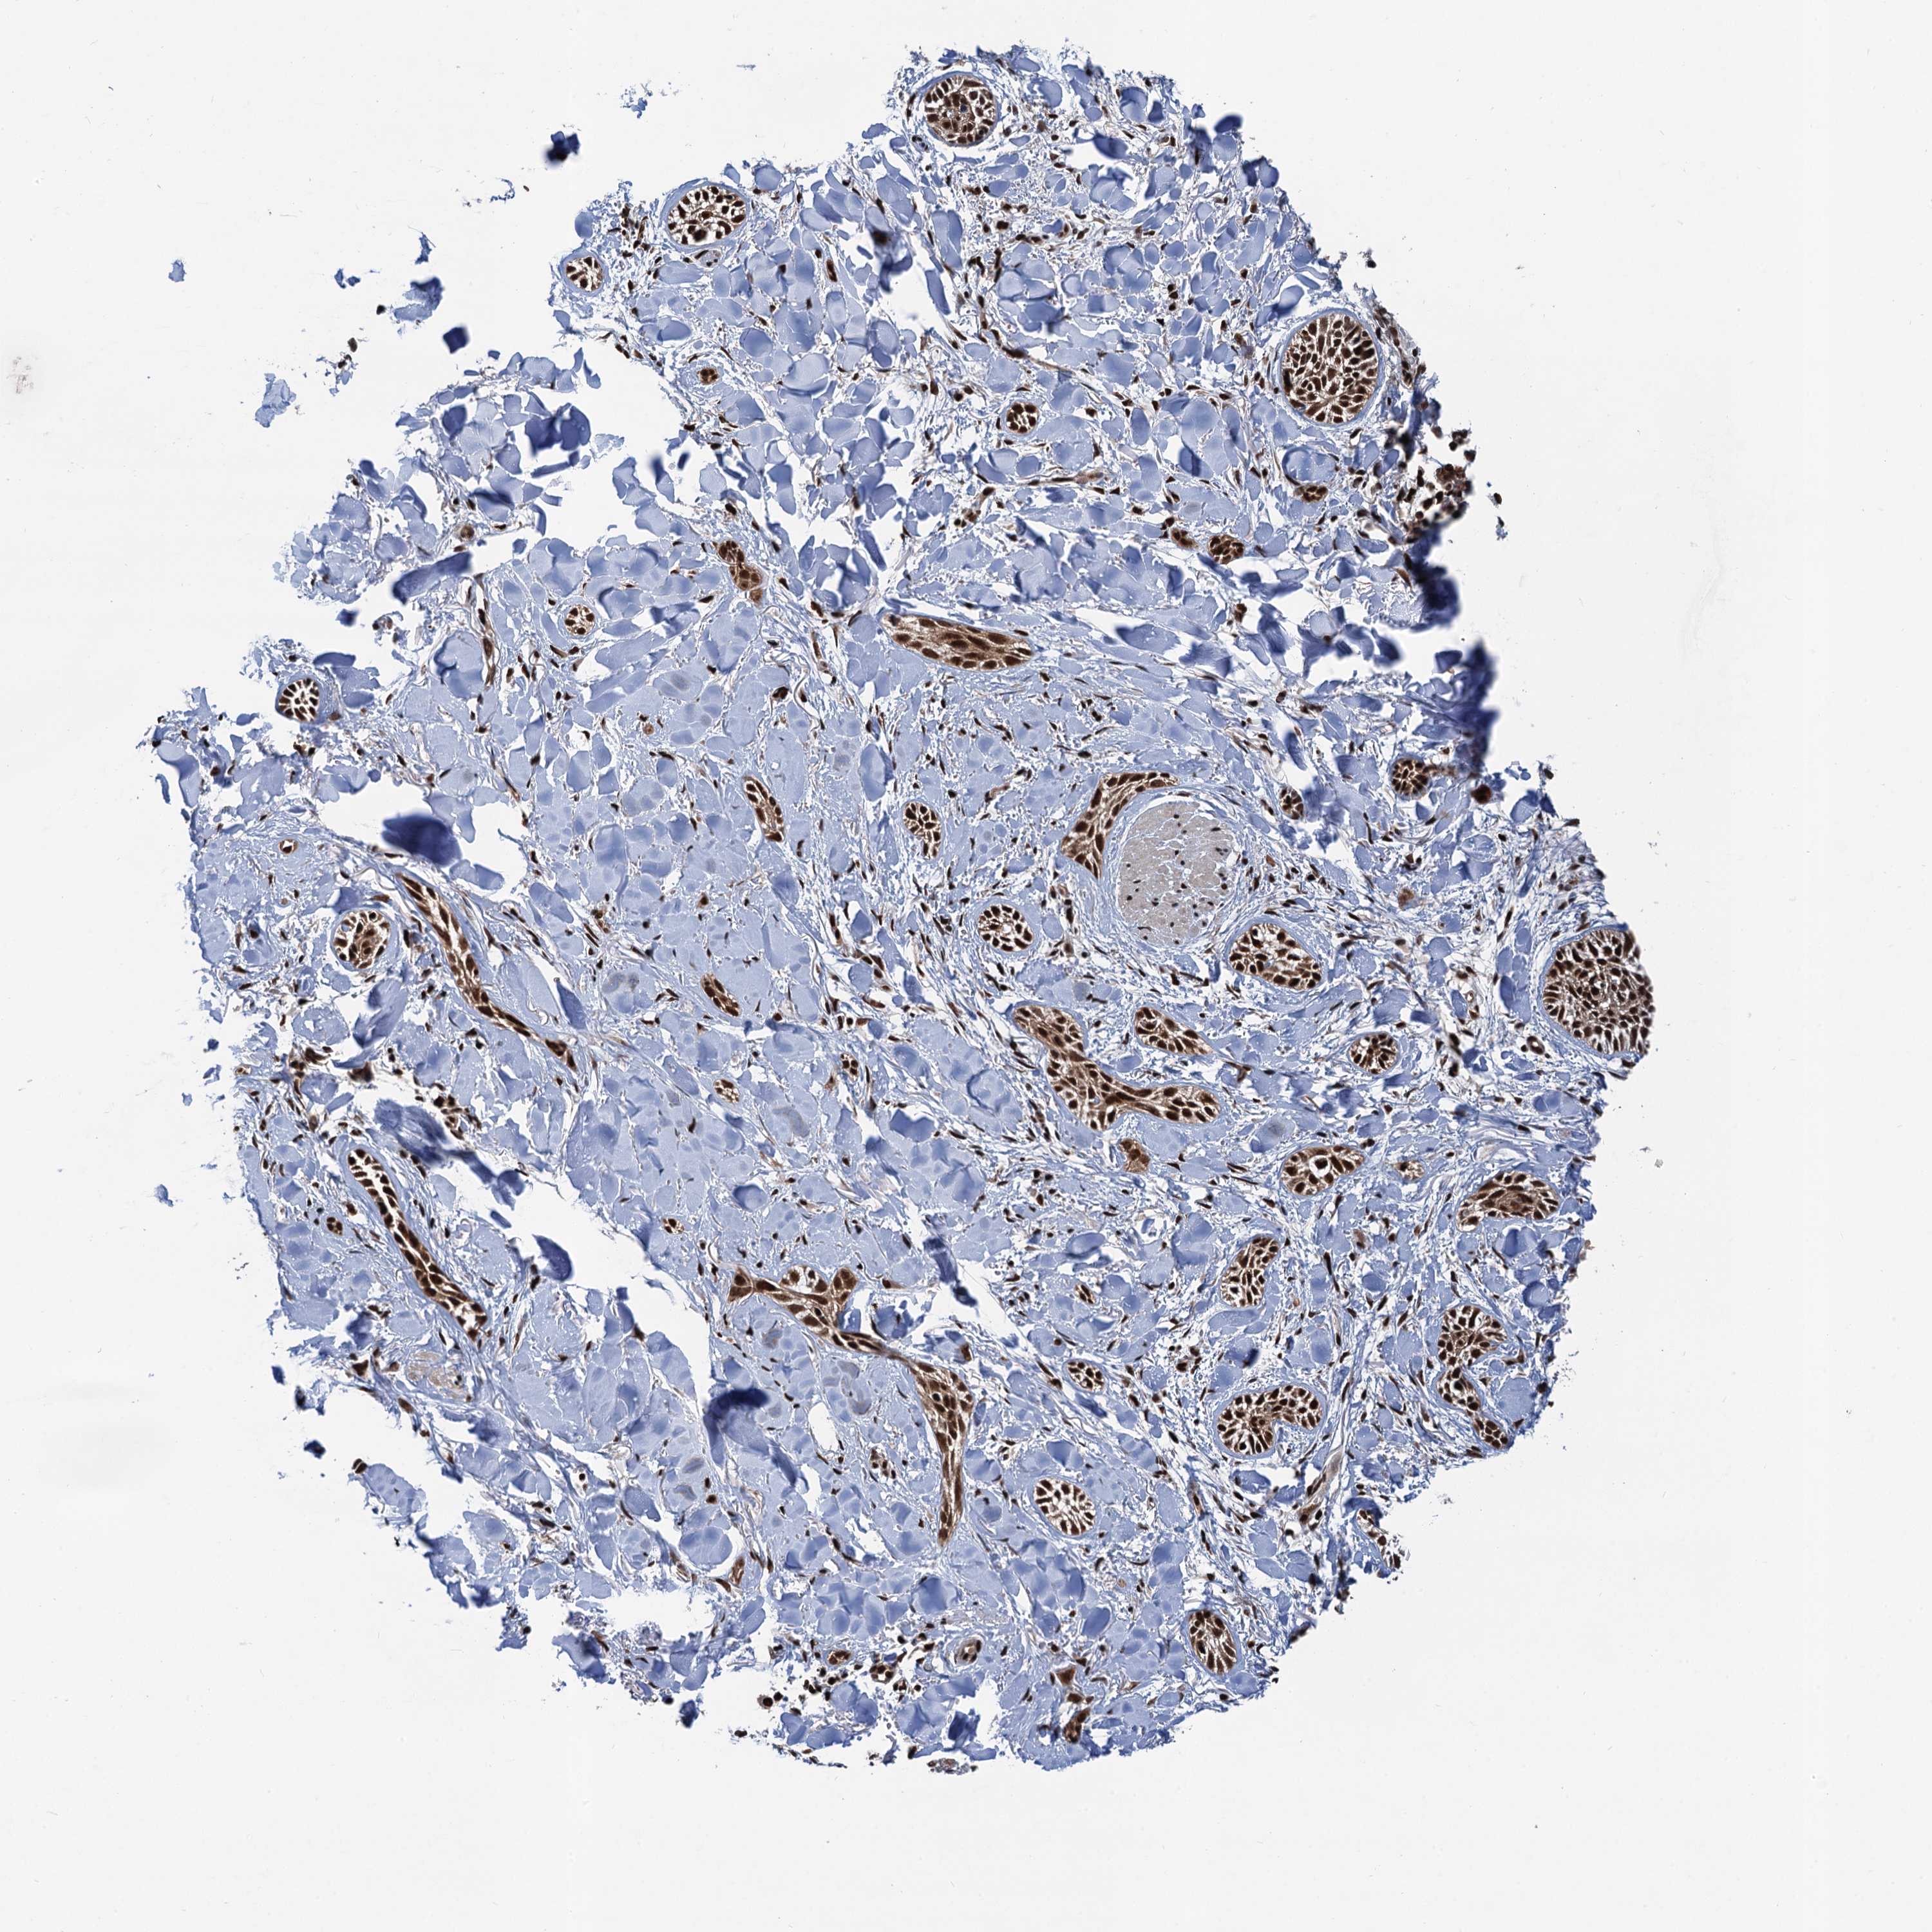

SKIN CANCER - Protein expressioni

A mouse-over function shows sample information and annotation data. Click on an image to view it in a full screen mode. Samples can be filtered based on level of antibody staining by selecting one or several of the following categories: high, medium, low and not detected. The assay and annotation is described here.

Antibody staining in the annotated cell types in the current human tissue is reported as not detected, low, medium, or high, based on conventional immunohistochemistry profiling in selected tissues. This score is based on the combination of the staining intensity and fraction of stained cells.

Each image is clickable and will lead to virtual microscopy that enables deeper exploration of all samples and also displays staining intensity scores, fraction scores and subcellular localization as well as patient and tissue information for each sample.

Antibody HPA040905

Squamous cell carcinoma, NOS